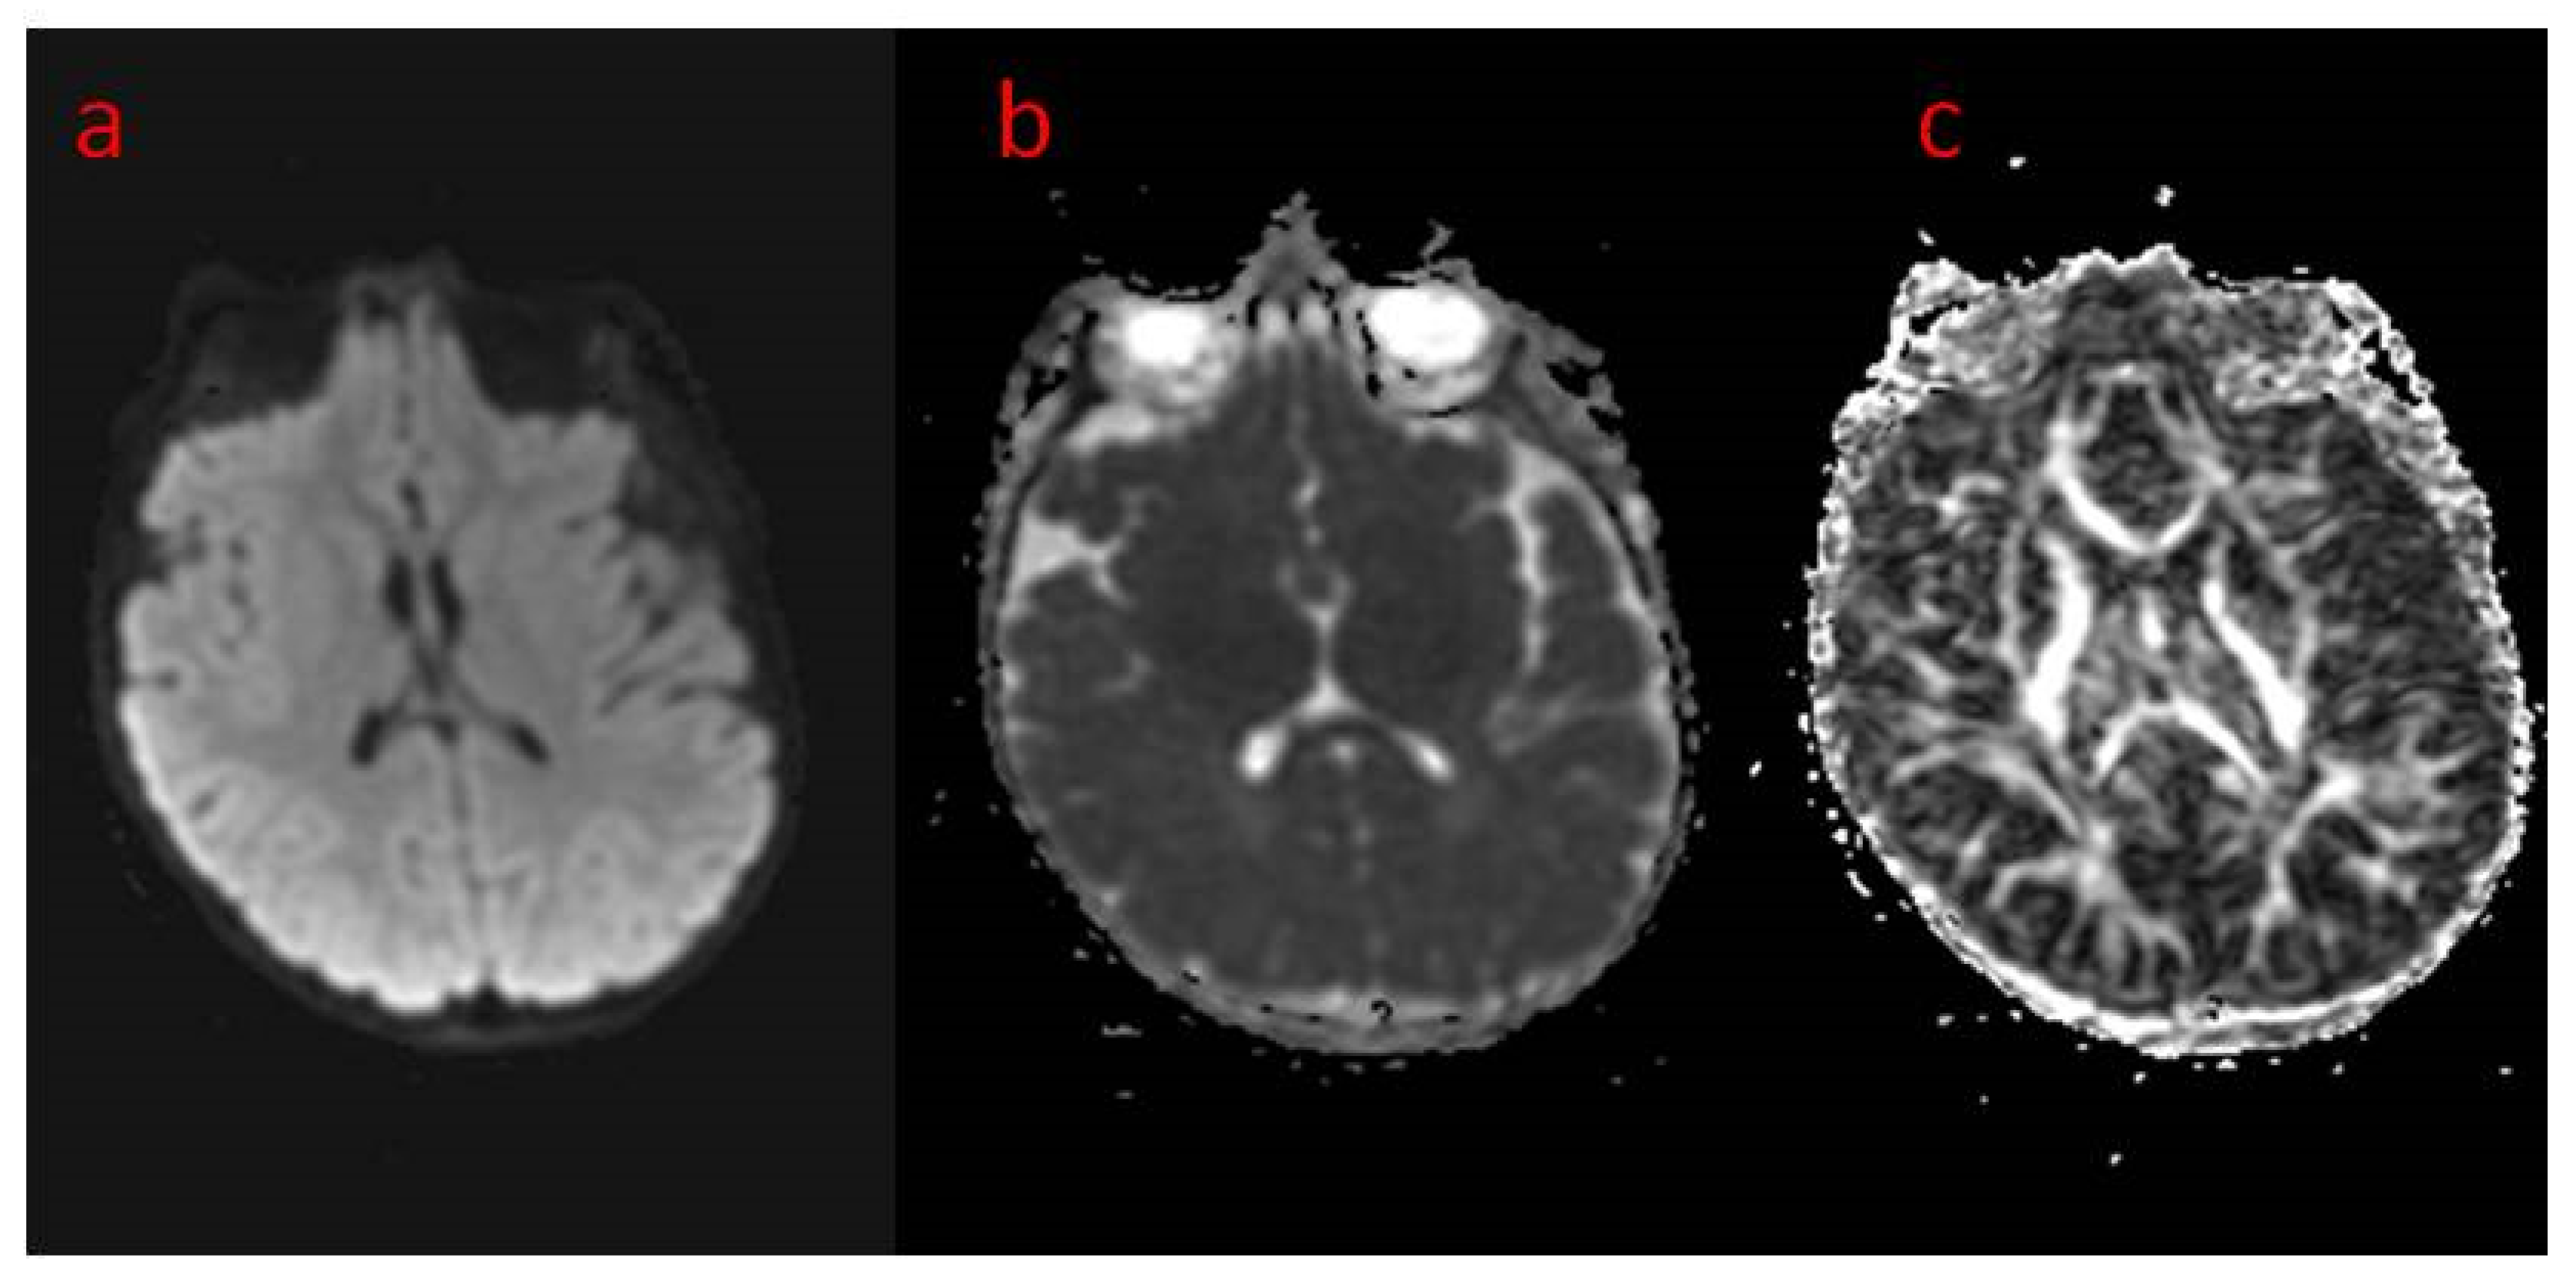

| 16 The present study | Areas of incomplete myelination (in the area of the triangles of the lateral ventricles and around the occipital horns) | Cortical visual impairment, poor eye contact, with movement disorder | Hypotonia, joint contractures | Severe global developmental delay | Dysphagia (only liquid food) | Difficult to treat, ASM resistance (valproic acid, topiramate, vigabatrin, phenobarbital, levetiracetam, phenytoin, clobazam, clonazepam, nitrazepam, lamotrigine, carbamazepine, and zonisamide), steroid therapy (adrenocorticotropic hormone, methylprednisolone—break), vagal nerve stimulation, ketogenic diet intolerance (due to reluctance to drink) |